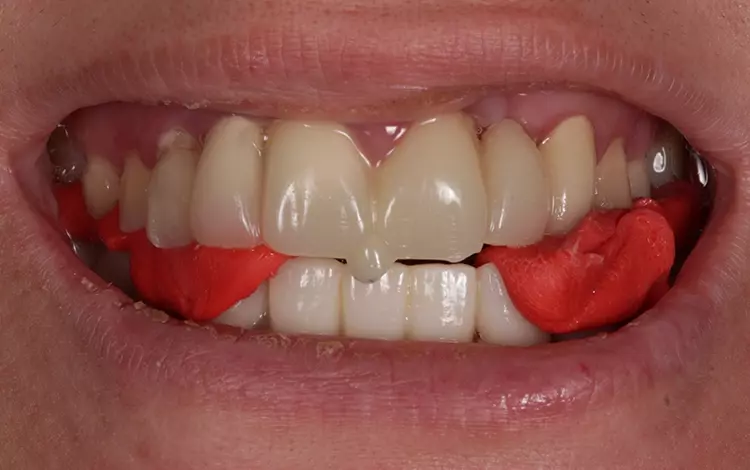

Nach Befundaufnahme inklusive klinisch/instrumenteller Funktionsanalyse und professioneller Zahnreinigung erfolgten eine Abformung zur Herstellung von Situationsmodellen, die Aufnahme des Fotostatus, eine Clinometerregistrierung, eine individuelle Gesichtsbogenübertragung, die Bissnahme in zentrischer Kondylenposition [16] nach Deprogrammierung der Kaumuskulatur mit einem Aqualizer (um die Patientin „zentrikfähig“ zu machen) mittels Frontjig und GC Bite Compound nach Gutowski [17] (Abb. 4). Es folgten ein Wax-up/Mockup (Abb. 5), eine Schienenvorbehandlung in zentrischer Kondylenposition (RP) und eine Hygienephase für 6 Wochen.

Es wurde ein neues Wax-up für den OK und UK mit einer Bissabsenkung zur Optimierung des Overbite und zur Gestaltung einer flacheren Okklusionsebene angefertigt. Die Präparation im OK zur Herstellung eines CAD/CAM-gefrästen OK-LZP mit Anpassung an die UK-Kauflächen mit durchsichtigem Silikonschlüssel und Komposit via neuem Waxup erfolgte für die Patientin wahlweise mit „schmalen“ und „breiten“ Frontzähnen. In einer erneuten Reevaluation nach 4 Wochen wurde die Austestung der Bisslage mittels klinischer Funktionsanalyse realisiert.